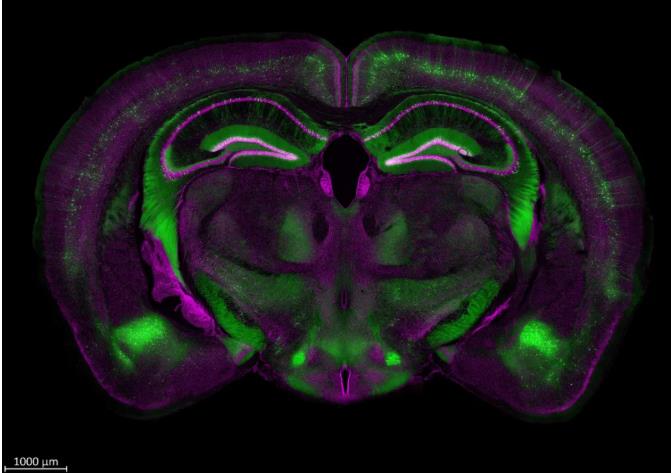

蔡司激光共聚焦顯微鏡作為生命科學實驗最常用的儀器之一,幾乎會出現在每個生命科學研究者的“ Materials and Methods ”中。蔡司激光共聚焦顯微鏡 LSM 7/8/9 係列以其高質量的成像結果深受生命科學科研工作者的喜愛,成為了蔡司的“明星產品”。

隨著科研手段的不斷升級,激光共聚焦顯微鏡也在不斷滿足我們越來越多的多維成像需求。但是,我們在實際操作時,難免會因為樣品 “罷工”,遇到一些抓狂時刻:

三維重構策略:Z-Stack

④ 速度優化。對於多色樣品三維重構,使用 Full Z-stack per Track 采集順序,可提高整體采集速度哦

⑤ 拍攝結果。軟件左側工具欄,3D 功能可以查看或導出渲染結果;Ortho 則可以獲取更大強度投影